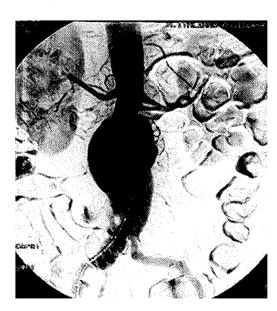

El propósito del estudio es el de analizar la factibilidad y la eficacia del tratamiento de exclusión endoluminal mediante la colocación de endoprótesis autoexpandible en el aneurisma de la aorta abdominal (AAA).

Entre agosto de 1998 y marzo de 2000 se colocaron 25 endoprótesis bifurcadas (Vanguard, Boston Scientific, USA y Talent, Medtronic, USA) en veinticinco pacientes, por presentar un AAA asintomático . La edad promedio fue de 70,5 años ; DS: 7,8 . Los procedimientos se realizaron bajo anestesia general en 23 pacientes y raquídea en los dos restantes .

El implante fue técnicamente exitoso en el 96% ; se registró una conversión quirúrgica . Se produjeron complicaciones menores inmediatas posprocedimiento (insuficiencia renal aguda autolimitada, angor sin modificaciones de enzimas ni eléctricas) . El seguimiento medio fue de 260 días. Leaks directos de tipo 1 : en dos pacientes (uno corregido a los tres meses con exclusión, con una extensión proximal y otro distal actualmente en control) . Se registraron un leak de tipo 2 que selló sin tratamiento y una oclusión de una rama que fue corregida con un bypass femoro-femoral . La exclusión primaria fue del 88% y la secundaria, del 96% . Hubo un óbito de causa relacionada en el seguimiento temprano y dos pacientes fallecieron de causa no relacionada (accidente cerebrovascular, insuficiencia respiratoria severa) en el seguimiento tardío .